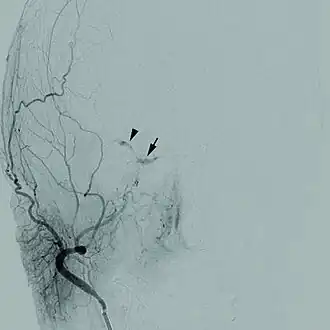

As doenças cerebrovasculares são um grupo de disfunções cerebrais relacionadas com a doença dos vasos sanguíneos que fornecem sangue ao cérebro. A hipertensão arterial é a causa mais importante que pode causar danos ao revestimento dos vasos sanguíneos ( o endotélio) expondo o colágeno onde as plaquetas se juntam para dar início a um processo de reparação que nem sempre é completo e perfeito. Com a hipertensão permanente, as alterações à estrutura dos vasos sanguíneos deixando-os mais estreitos, rígidos, deformados e desiguais, sendo mais vulneráveis às flutuações da pressão arterial. Uma queda na pressão arterial durante o sono pode levar à redução acentuada do fluxo sanguíneo no estreitamento dos vasos sanguíneos, causando um acidente vascular cerebral de manhã, com um aumento súbito da pressão arterial, podendo para além disso provocar uma hemorragia intracraniana. Principalmente as pessoas que são idosas, diabéticas, fumantes ou que tenham doenças do coração têm um risco à doença cerebrovascular. Todas as doenças relacionadas com a disfunção arterial podem ser classificadas como doença macrovascular. Este é um estudo simplista pelo qual as artérias estão bloqueadas pelos depósitos gordos ou por um coágulo. Os resultados da doença cerebrovascular pode incluir um AVC, ou mesmo por vezes um acidente vascular cerebral hemorrágico. Isquemia ou outras disfunções dos vasos sanguíneos podem afectar durante um acidente vascular cerebral.